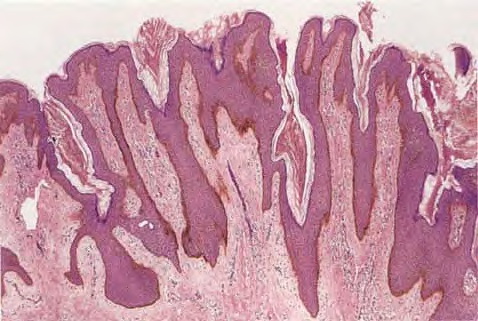

Epidermal naevus = الوحمة البشروية